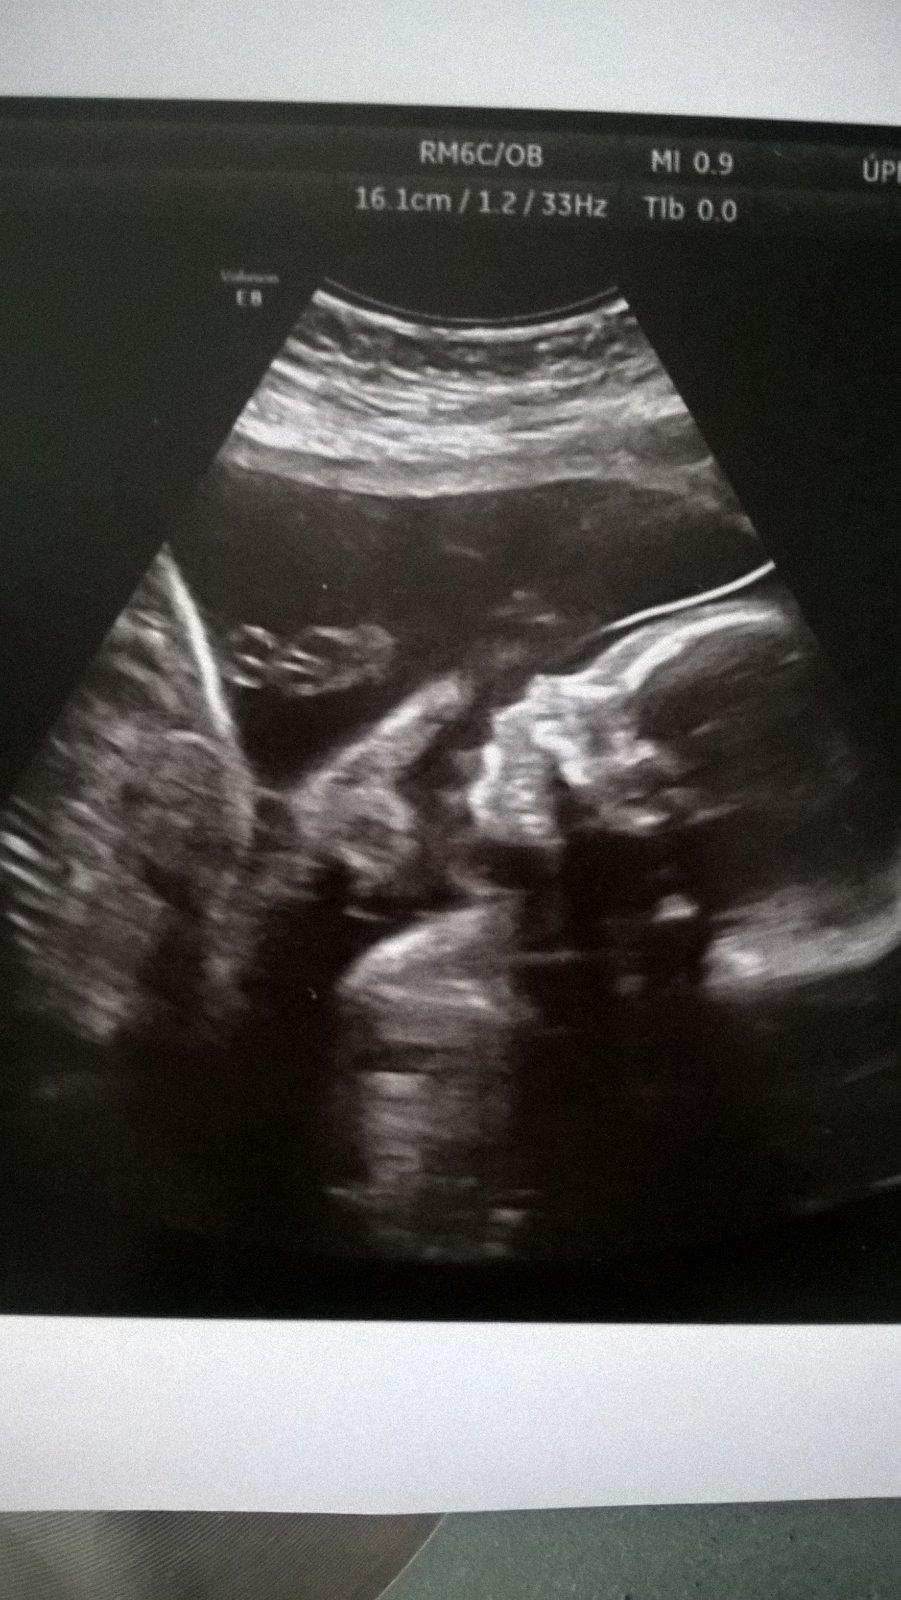

Tak dneska den jedna baseň😊 kluci jsou naprosto v poradku, mensi dohani vetsiho,coz je uplne super🙂 jsou dulezití a oba se drzely za hlavu😁mam z nich radost, oba jsou hlavickou dolu,coz je super ale moje zebra uz dva dny trpí🙂manzel rika ze mi devastuji vnitrnosti😀(23+4)